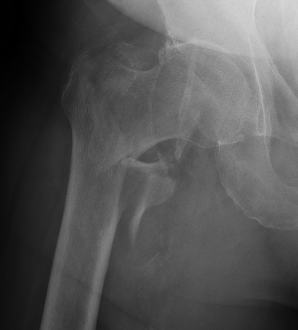

Isolated GT Fracture

Stability

Depends on medial cortical reduction

Unstable (AO 31.A2 + 31.A3)

- intact lateral wall

- posteromedial cortical fracture